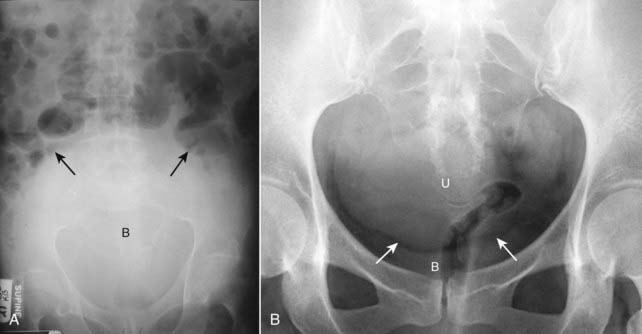

Figure 13-25 Normal urinary bladder.

Close-up of the pelvis shows enough perivesical fat to make the outline of the urinary bladder visible (solid white arrows). In males, the sigmoid colon usually occupies the space just above the bladder (solid black arrow); in females, the soft tissue above the bladder may be either the uterus or sigmoid colon.

Figure 13-26 Distended urinary bladder and enlarged uterus.

A, The distended bladder (B) is a soft tissue mass that ascends from the pelvis into the lower abdomen displacing the bowel into the midabdomen (solid black arrows). This was a 72-year-old man with bladder outlet obstruction from benign prostatic hypertrophy. B, The uterus (U) is slightly enlarged. It can be distinguished from the bladder because there is a fat plane (solid white arrows) seen between it and the urinary bladder (B) below it.